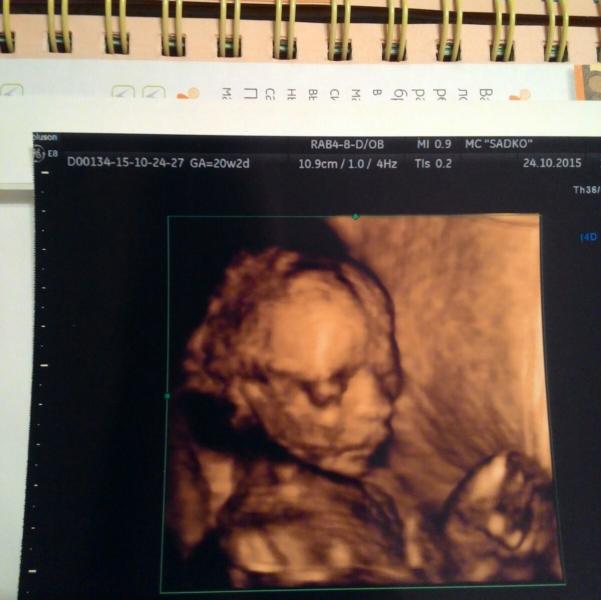

хотите новости с полей?! будут. у нас мальчик. приметы врут, неразвитое материнское чутье тоже! главное что мы здоровы и все идет по плану.